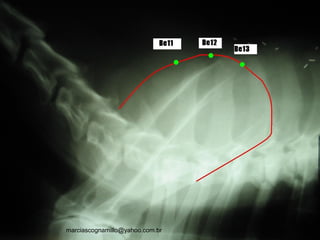

P B13 Per B14

C B15 F B18

VB B19 BP B20

E B21 TA B22

R B23 IG B25

ID B27 B B28

Pontos de assentimentoPontos de assentimento::

B 13 T3 – T4

1.5 tsun lateral à borda caudal do processo

espinhoso da 3ª vértebra torácica

Assentimento do P

Lung Shu Point

B 14 T4 – T5

espinhoso da 4ª vértebra torácica

Assentimento do Per

Pericardium Shu Point

B 15 T5 – T6

espinhoso da 5ª vértebra torácica

Assentimento do C

Heart Shu Point

PULA UMA VÉRTEBRA!